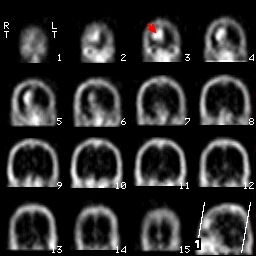

這是一個right frontal Lobe發現腫瘤的圖片,在這3個方向的切面中都能夠見到在大腦右前葉處出現了Tc-99m-DTPA的堆積影像,另外一張圖則是利用透視法所處理出來的3D影像,清楚的顯現出腫瘤的位置。

冠狀切面coronal